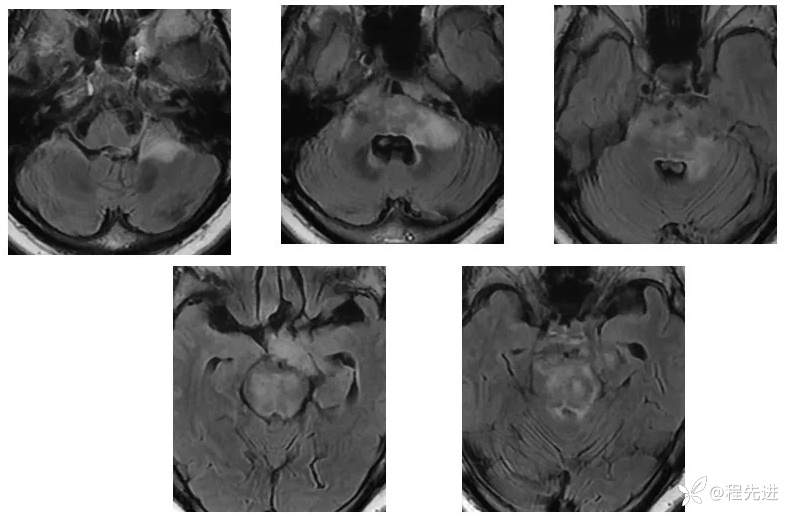

【现病史及既往史】:右眼斜视及视力下降7个月,右眼脸下垂3个月,右眼失明1个月

查体:生命体征平稳,右眼脸下垂,右眼失明,左眼内收位,外展受限,光反应迟钝,左侧角膜反射减弱,左侧听力下降,左面部痛温觉减弱无吞咽困难,无饮食饮水呛咳,伸舌舌尖左偏。